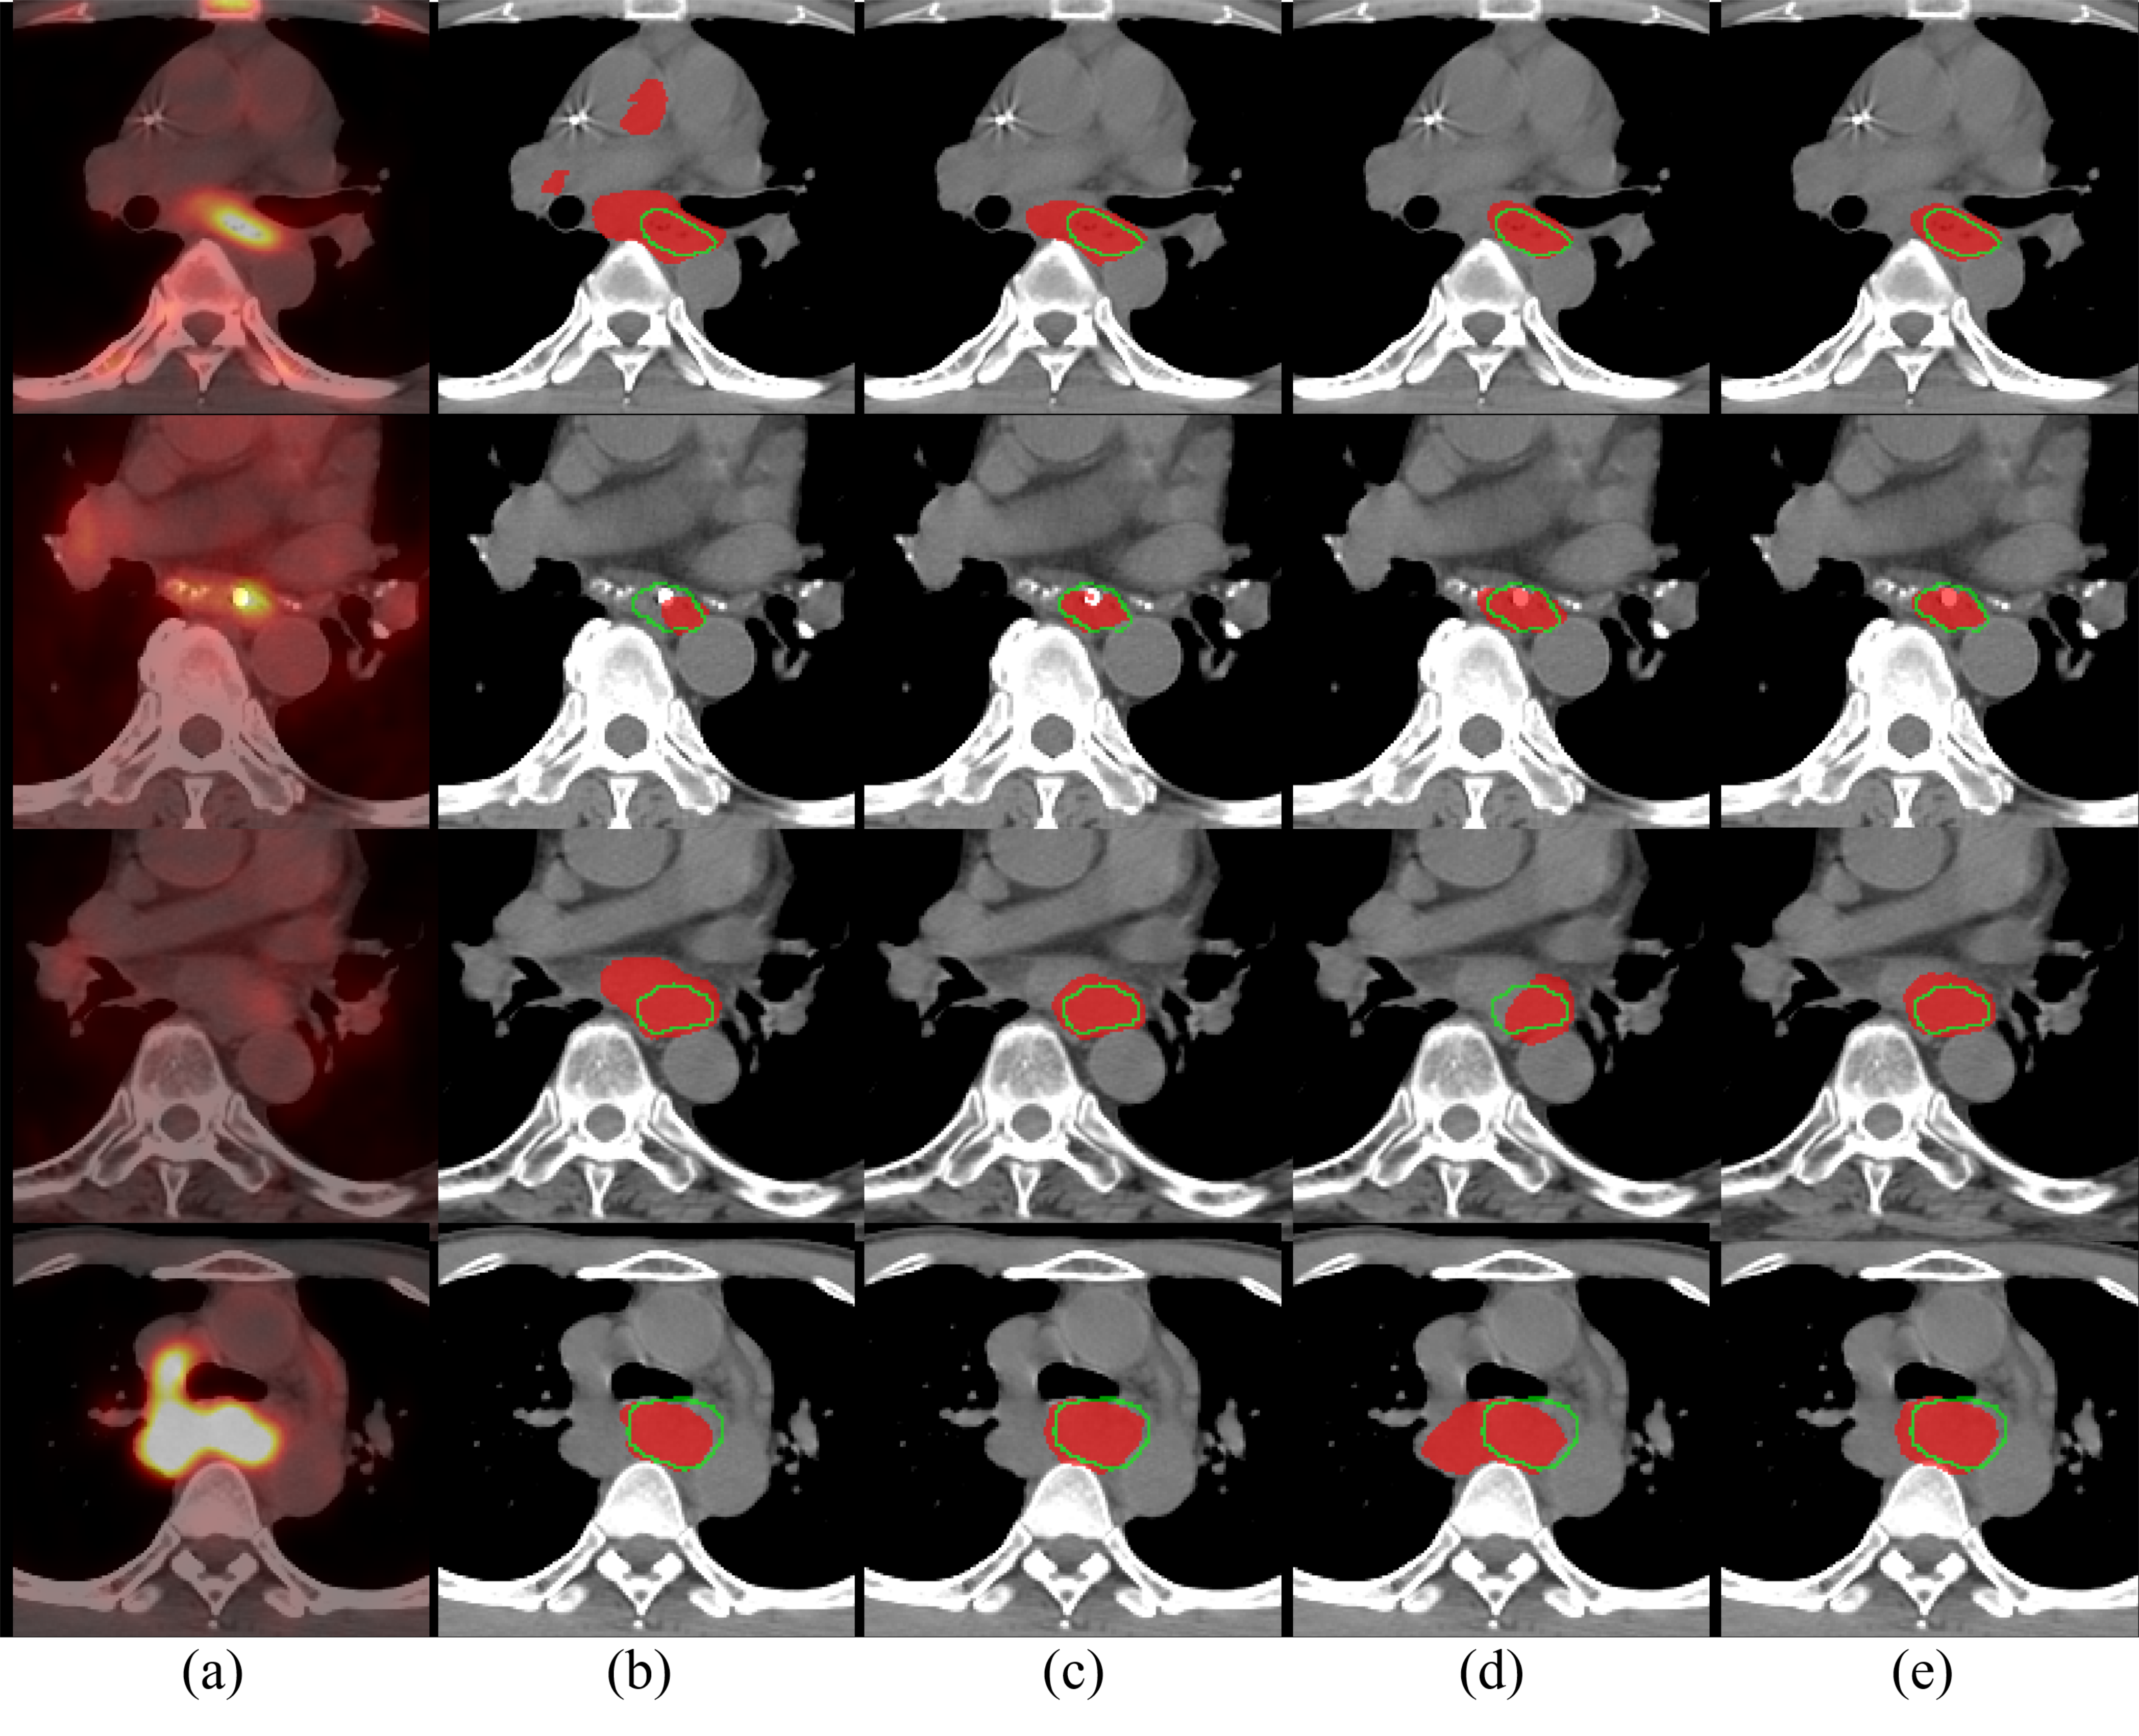

Refer to caption

Figure 4: Qualitative results of esophageal GTV segmentation. (a) RTCT overlayed with the registered PET channel; (b) GTV segmentation results using RTCT images with DenseUNet [15]; (c) Our results using Eq. (1), i.e., RTCT-only stream using the proposed \acPSNN model; (d) Our results using Eq. (2) with \acPSNN, i.e., \acsEF of PET+RTCT images; (e) Our final GTV segmentation using Eq. (3) with \acPSNN, i.e., \acsEF and \acsLF of PET+RTCT images. Red masks indicate automated segmentation results and green boundaries represent the ground truth. The first two rows demonstrate the importance of PET as using RTCT alone can cause under- or over-segmentation due to low contrast. The last two rows show cases where under- or over-segmentation can occur when the PET imaging channel is spuriously noisy. In all cases, the final \acEF+\acLF based GTV segmentation results achieve good accuracy and robustness.

Table 1 also outlines the performances of three deep models under different imaging configurations. Several conclusions can be drawn. First, all three networks trained using the \acEF of Eq. (2) consistently produce more accurate segmentation results than those trained with only \acRTCT, i.e., Eq. (1). This validates the effectiveness of utilizing \acPET to complement \acRTCT for \acGTV segmentation. Second, the full two-stream chained fusion pipeline of Eq. (3) provides further performance improvements. Importantly, the performance boosts can be observed across all three deep \acpCNN, validating that the two-stream combination of \acEF and \acLF can universally improve upon different backbone segmentation models. Last, the best performing results are the \acPSNN model combined with chained \acEF+\acLF, demonstrating that each component of the system contributes to our final performance. When compared to the previous state-of-the-art work of \acGTV segmentation, which uses DenseUNet applied to \acRTCT images [15], our best performing model exceeds in all metrics of \acDSC, \acHD, and \acASD by 11%percent1111\%, 81.9mm81.9𝑚𝑚81.9mm and 2.0mm2.0𝑚𝑚2.0mm remarked margins (refer to Table 1), representing tangible and significant improvements. Fig. 4 shows several qualitative examples visually underscoring the improvements that our two-stage \acPSNN approach provides.